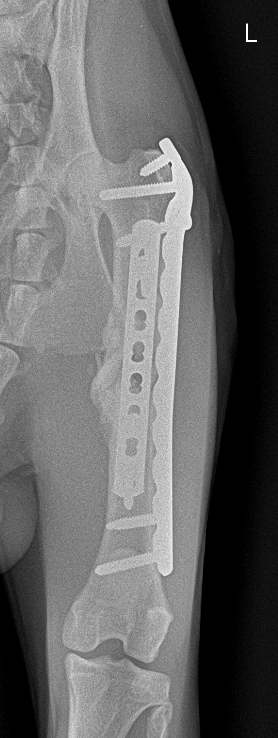

術後1ヶ月がたった為、手術をしていただいた病院に検診に行ってまいりました。

結果としては、かなり順調に回復しているとのことです!!

回復が思っていたよりも早く、先生も驚かれておりました!

画像だと少しわかりにくいかもしれませんが、骨が癒着しぶらぶらだった状態からしっかりと固まってきております。

術後1ヶ月